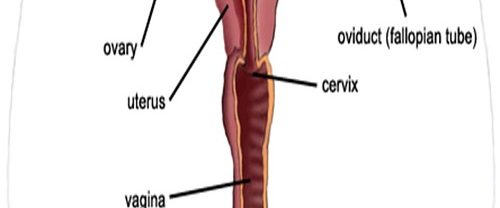

Ürojinekoloji Nedir? Ürojinekoloji, üroloji ve jinekoloji disiplinlerinin birleşiminden oluşan bir tıp dalıdır. Bu alan, kadın üreme sistemi ve idrar yollarıyla ilgili sağlık sorunlarını inceleyen ve tedavi eden bir uzmanlık alanıdır. Kadın anatomisi gereği idrar yolları ve üreme organları birbirine yakın olduğundan, bu alan iki farklı tıp uzmanlığının kesişim noktasında yer alır. Ürojinekolojinin Kapsamı Ürojinekoloji, kadınların…

Myomektomi Nedir? Myomektomi, rahimdeki miyomların cerrahi olarak çıkarılması işlemidir. Miyomlar, rahim duvarının kas dokusundan oluşan benign (iyi huylu) tümörlerdir. Bu tür tümörler genellikle kadınların üreme çağında görülür ve genellikle hormonlarla ilişkilidir. Miyomlar, adet döneminde artan kanama, ağrı ve pelvik baskı gibi semptomlara neden olabilir. Büyük veya belirli bir konumda bulunan miyomlar ayrıca hamilelik sırasında komplikasyonlara…

Kadın İnfertilitesi Nedir? Kadın infertilitesi, bir kadının istediği şekilde bir çocuk sahibi olamama durumudur. İnfertilite, genellikle bir yıl boyunca düzenli cinsel ilişkiye rağmen hamilelik elde edilememesi olarak tanımlanır. Kadın infertilitesi, çeşitli faktörlerden kaynaklanabilir ve üreme sistemine yönelik çeşitli sorunları içerebilir. Kadın İnfertilitesinin Nedenleri Nelerdir? Kadın infertilitesinin çeşitli nedenleri olabilir. Bunlar arasında şunlar bulunur: Yumurtalık sorunları:…

İnfertilite Kısırlık Nedir? İnfertilite Kısırlık, bir çiftin düzenli cinsel ilişkiye rağmen gebelik elde edememesi durumunu ifade eder. Bu durum, çiftin bir yıl boyunca düzenli olarak korunmasız cinsel ilişkiye girmesine rağmen hamilelik oluşmamasıyla tanımlanır. İnfertilite, hem kadın hem de erkek faktörlerinden kaynaklanabilir ve çeşitli nedenlerle ortaya çıkabilir. Kadınlarda İnfertilite: Kadınlarda İnfertilite Kısırlık, yumurtalıkların düzgün çalışmaması, yumurtalık…

Histerektomi Rahim Alınması Nedir? Histerektomi Rahim Alınması, bir kadının rahminin tamamen veya kısmen cerrahi olarak çıkarılması işlemidir. Bu prosedür, çeşitli sağlık sorunlarına çözüm olarak uygulanabilir. Rahmin alınması, genellikle aşağıdaki durumlar için gereklidir: Rahim Kanseri veya Prekanseröz Durumlar: Rahim kanseri teşhisi konulmuş veya rahim hücrelerinde kanser öncüsü değişiklikler tespit edilmişse, histerektomi tedavi seçeneklerinden biri olabilir. Myomlar…

Endometriozis Nedir? Endometriozis, kadınların üreme sistemini etkileyen bir sağlık sorunudur. Normalde rahim iç tabakasını oluşturan dokunun, rahim dışında (genellikle karın boşluğunda) bulunması durumunu ifade eder. Bu durumda, adet döneminde rahim iç tabakasına benzer şekilde doku büyür, kalınlaşır, kanar ve sonunda dökülür. Ancak, bu doku vücut dışında olduğu için dökülen kan vücuttan atılamaz ve çevredeki dokulara…